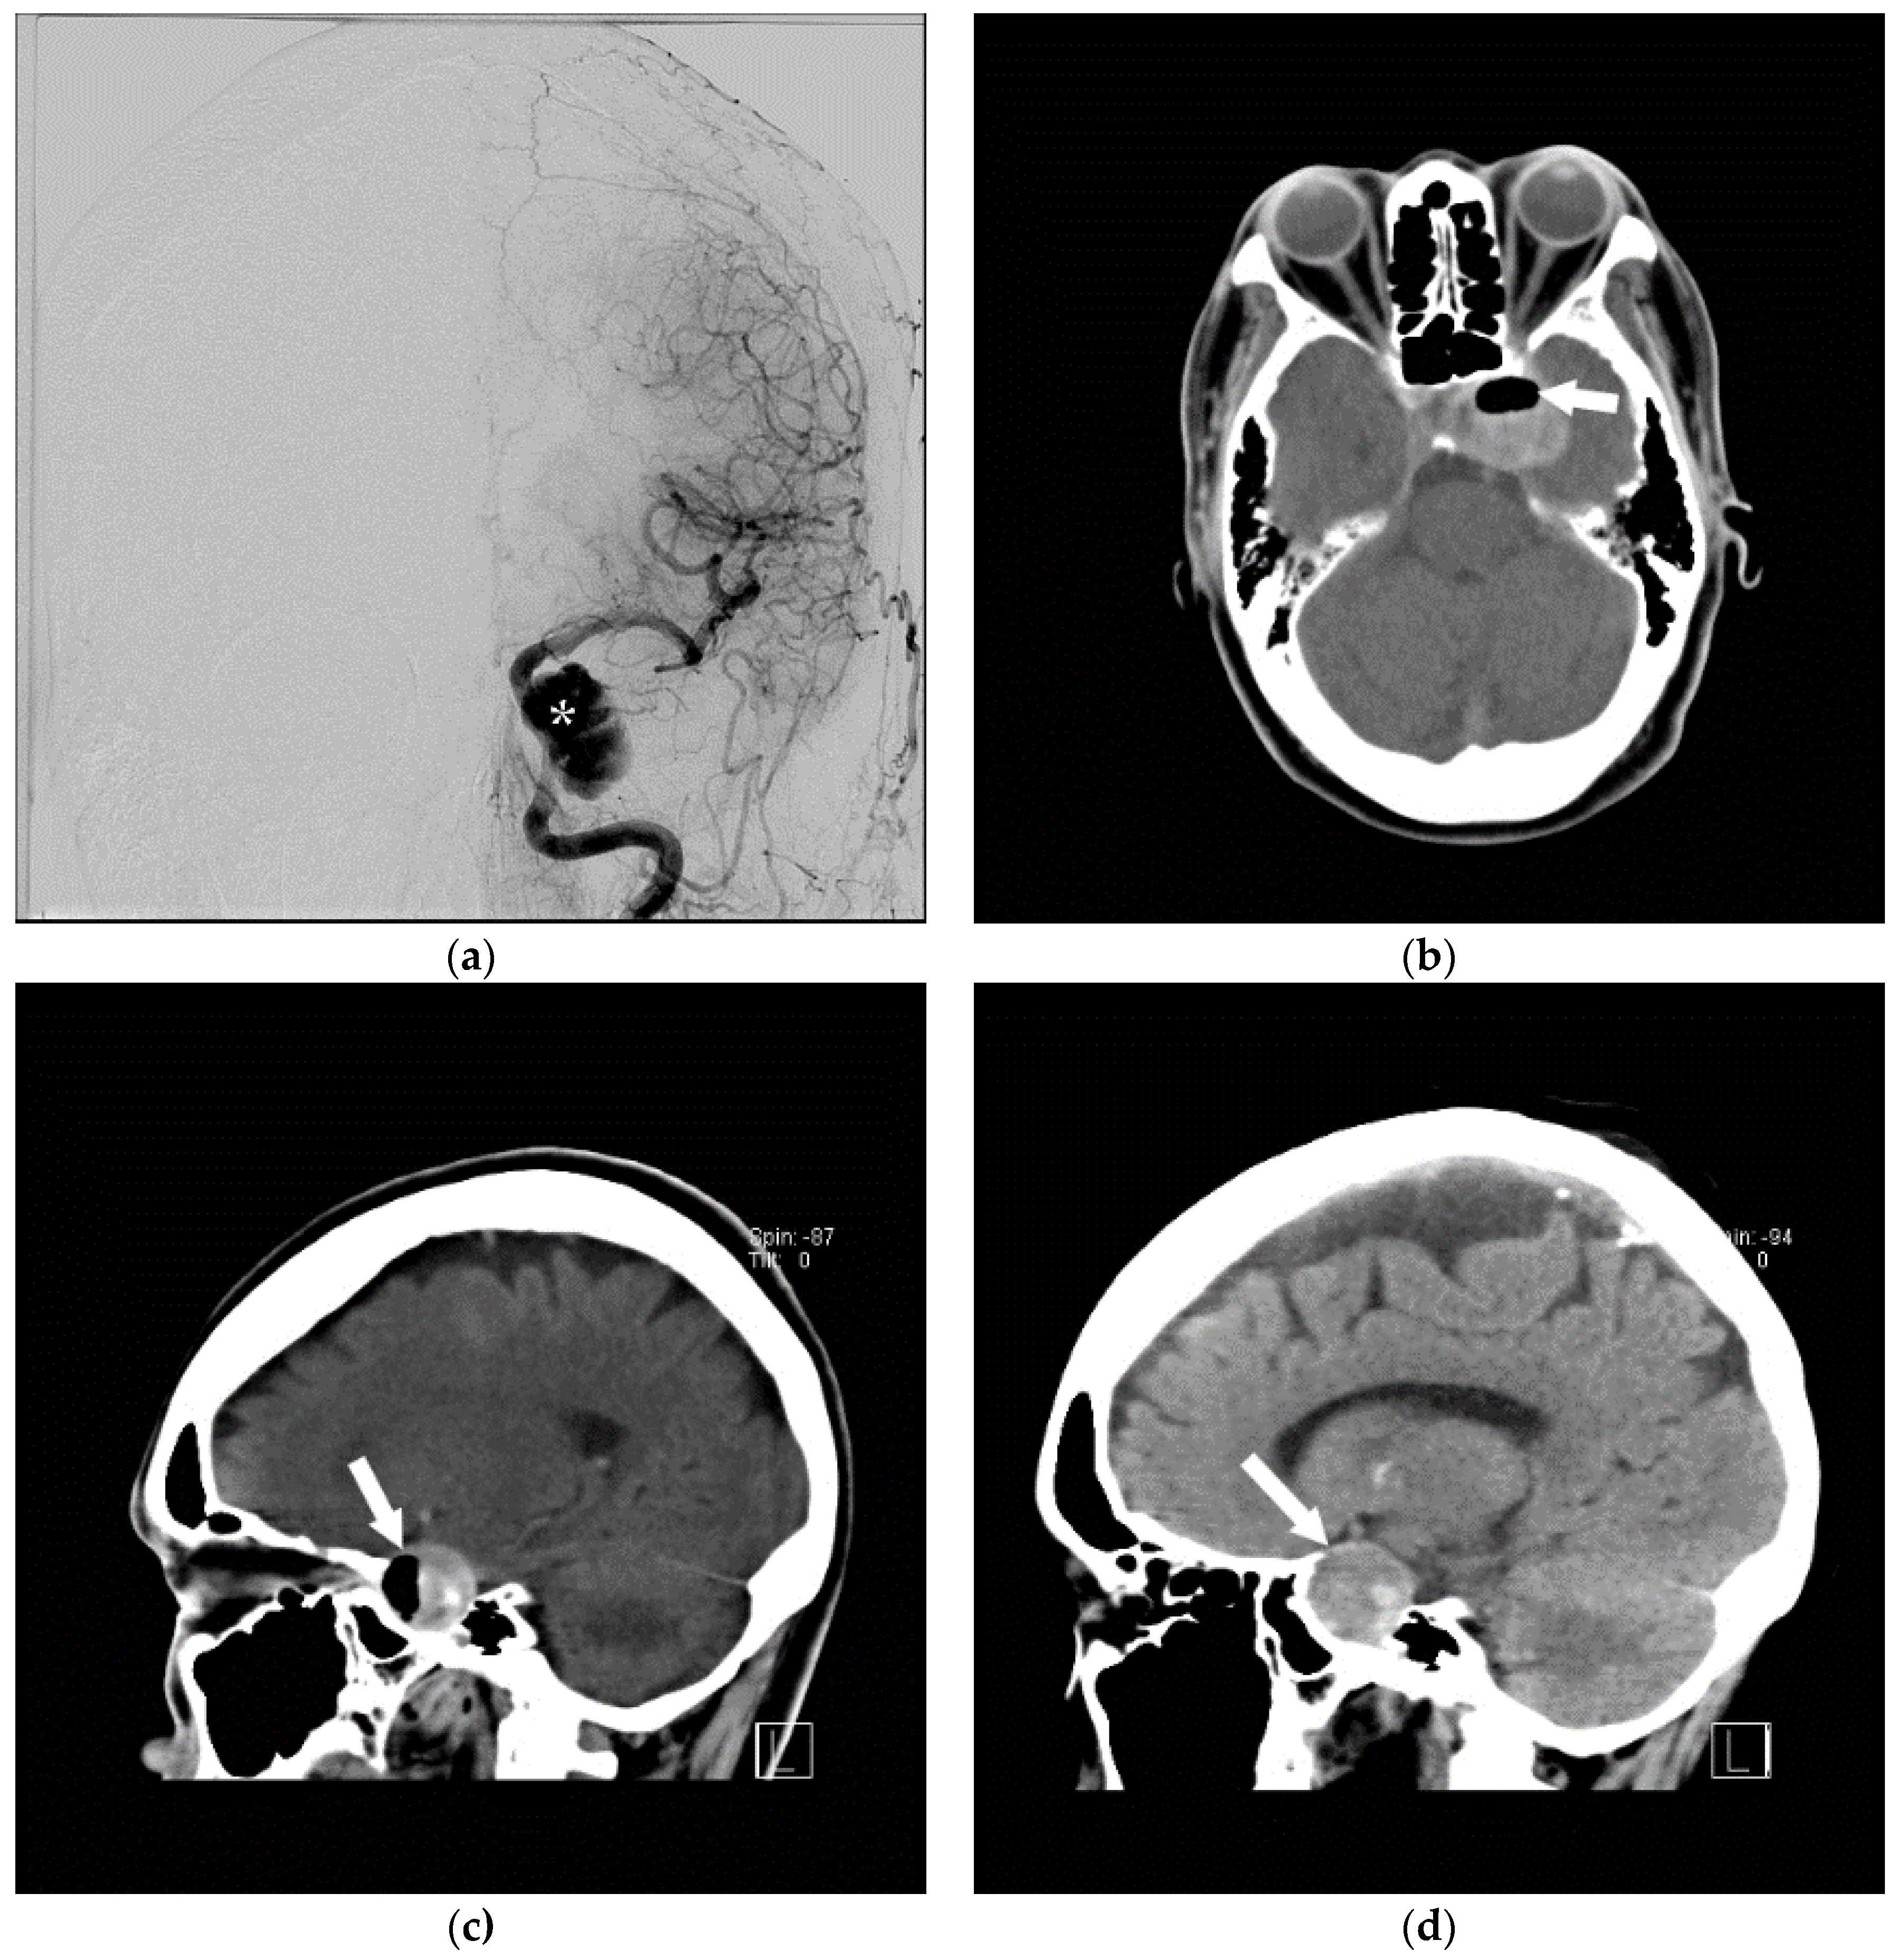

Figure 10.

The successful use of a hyperbaric oxygen therapy (HBOT) is outlined in this case, in which a 69-year-old female with a history of suspected lung cancer underwent a CT-guided lung biopsy at an outside facility (a). During the procedure, the patient suffered a cardiorespiratory arrest. An immediate CT (b) revealed a right pneumothorax (arrow), together with air in the right pulmonary vein (arrowhead). Additional images from the CT scan (c,d), revealed air in the right coronary artery (black arrow), the ascending thoracic aorta (white arrow) and the epidural veins (arrowhead). The patient was initially unresponsive and required cardiopulmonary resuscitation. A non-contrast CT brain (e) was performed, revealing air scattered in the vessels overlying the right cerebral hemisphere (arrowheads). Subsequent MRI of the brain confirmed multiple areas of acute infarction in the right cerebral and cerebellar hemispheres. Axial T2 (f) and DWI (g) images of the brain demonstrated acute areas of infarction in the right cerebellum. The patient required ICU management and HBOT.